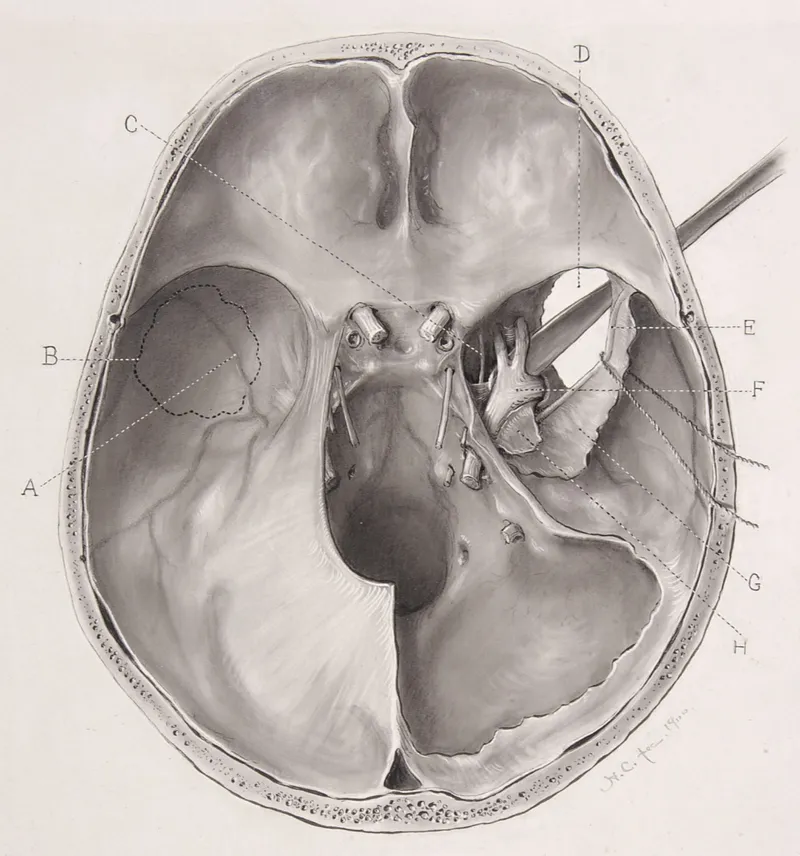

The anterior skull base extends from the frontal bone to the sphenoid ridge, encompassing the cribriform plate and orbital roofs. This region houses the olfactory apparatus and provides access to frontal lobe pathology. Surgical violations here risk CSF leaks in 15-25% of cases and anosmia in 30-40% of extensive resections.

The middle skull base represents the most complex surgical territory, housing the sella turcica, cavernous sinuses, and temporal bone structures. This region contains 60% of skull base pathology and requires multimodal approaches for optimal outcomes.

The posterior skull base encompasses the clivus, foramen magnum, and cerebellopontine angle. This region presents unique challenges due to brainstem proximity and vertebrobasilar circulation. Surgical approaches here demand microsurgical precision with zero tolerance for vascular injury.

Lateral skull base approaches encompass multiple surgical corridors including retrosigmoid, translabyrinthine, and middle fossa routes. Approach selection depends on hearing preservation goals, tumor size, and anatomical considerations.